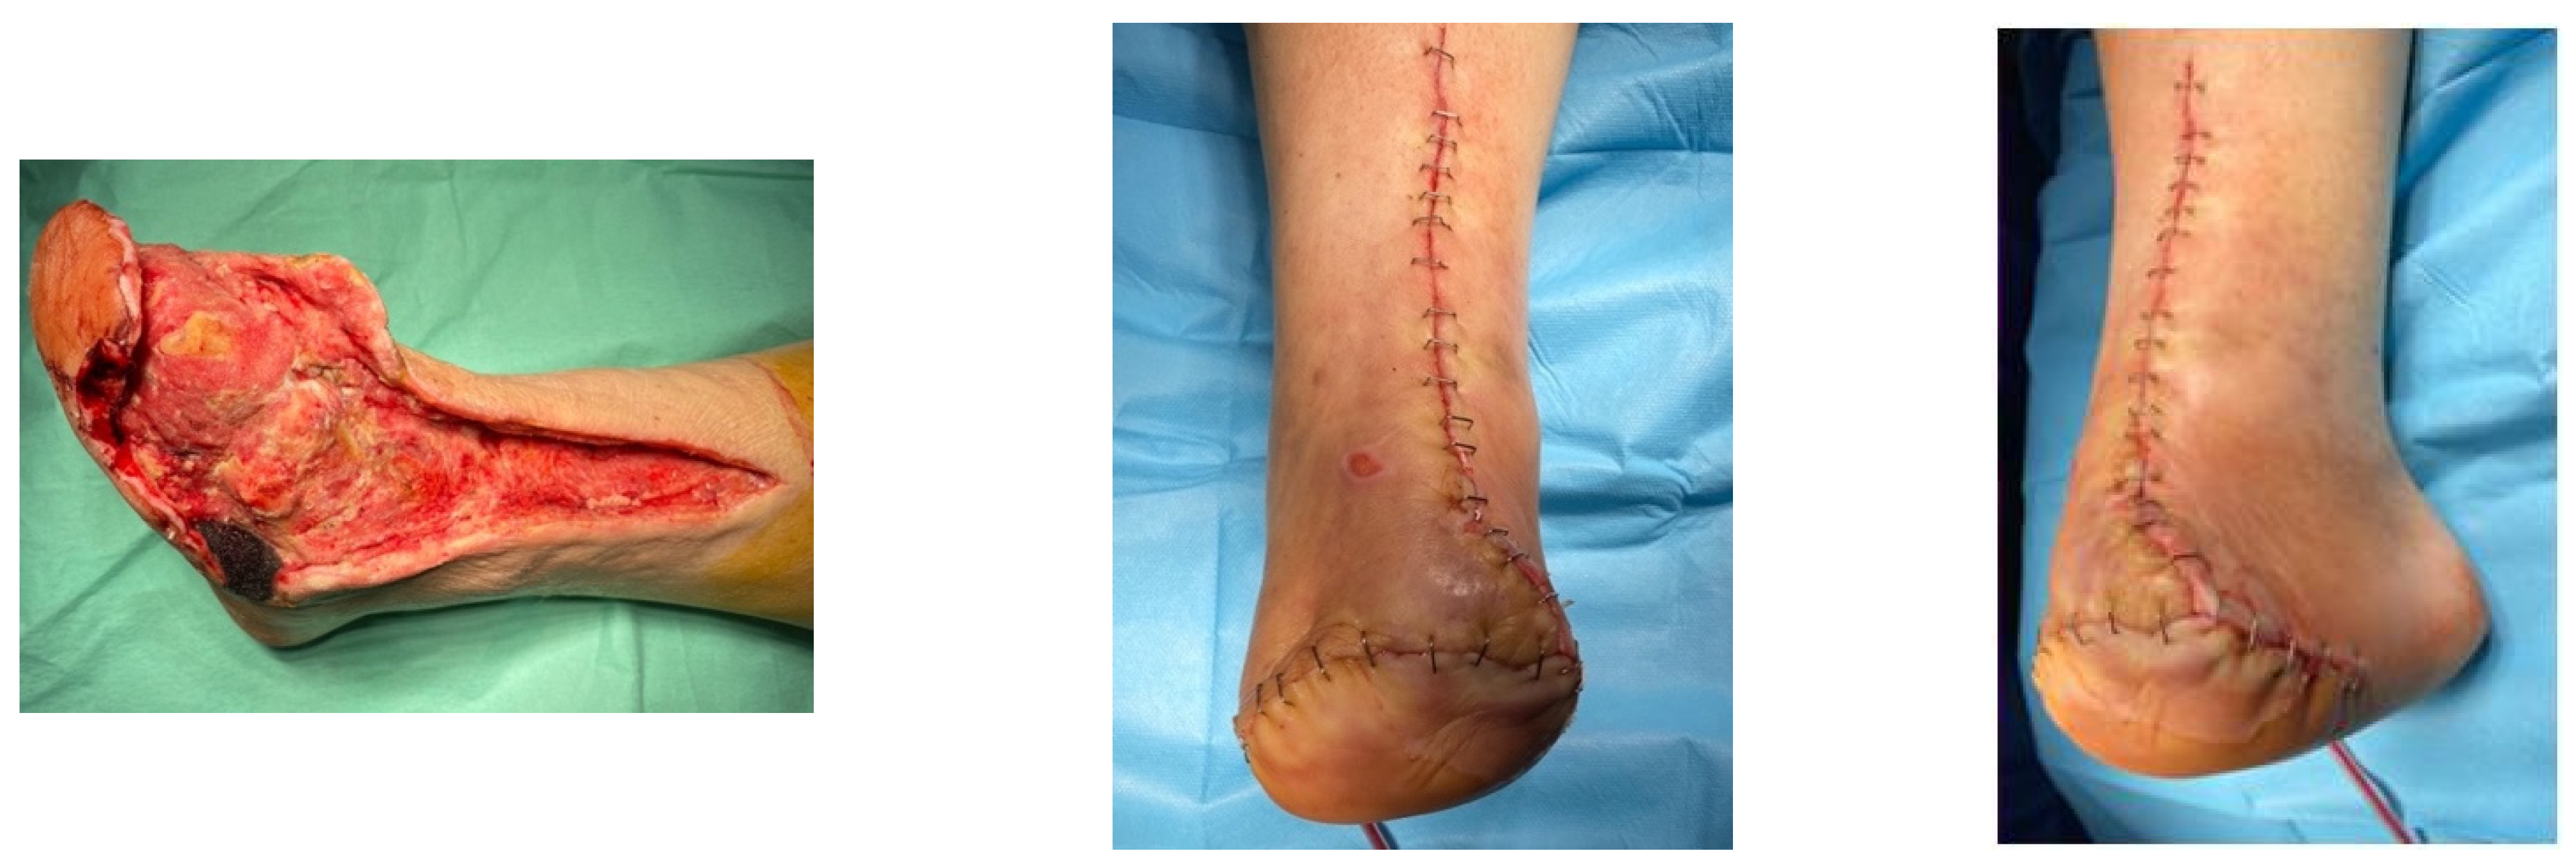

4.2. Case 2—Indirect Revascularization-Major Amputation